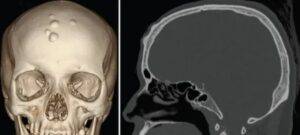

O que é um Osteoma? O osteoma, um tumor ósseo completamente benigno que se forma quando células ósseas saudáveis começam a se multiplicar de forma